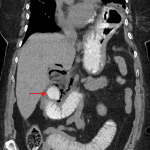

Indication: Concern for bowel obstruction

- Large hiatal hernia containing the gastric fundus and a portion of the gastric body

- Marked distension of the stomach and proximal small bowel with gradual tapering to normal caliber in the mid jejunum

- Fecalization of contents in the proximal jejunum

- Superiorly-directed diverticulum arising from the distal second segment of the duodenum with marked mural thickening and surrounding inflammatory changes with intermixed locules of extraluminal gas

- Periduodenal fat strand extends about the pancreatic head, though the pancreas is otherwise normal in appearance

- Perforated duodenal diverticulum

Perforated duodenal diverticulum with adjacent inflammatory changes and small volume pneumoperitoneum. No loculated intraabdominal fluid collection. Recommend surgical evaluation.

Proximal small bowel dilation may represent small bowel obstruction (which could be a cause for diverticular perforation) or ileus secondary to the nearby inflammation.